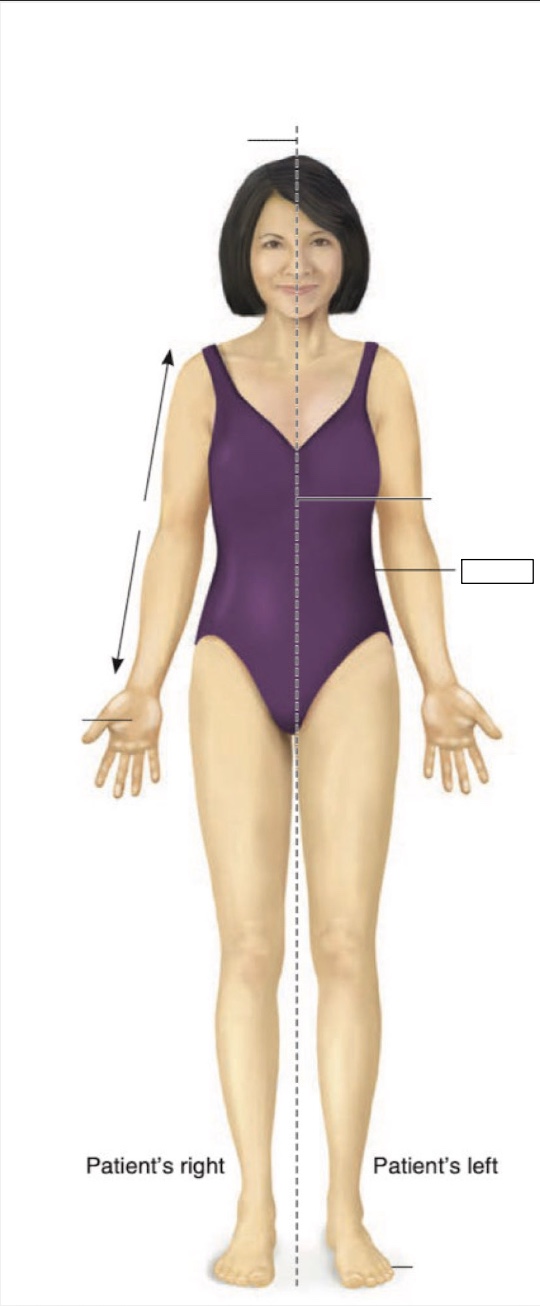

Posterior

Anterior

Superior

Inferior

Midline

Proximal

Distal

Palmar

Medial

Lateral

midsternal line

anterior axillary line

midclavicular line